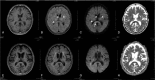

Lessons: His condition was atypical of TS-associated encephalopathy because of the long clinical course. Reversible splenial lesion was visible using brain imaging. In some cases of TS, disturbance of consciousness can be protracted for several months, but it is reversible. Therefore, it is necessary to judge the long-term neurological outcome carefully.